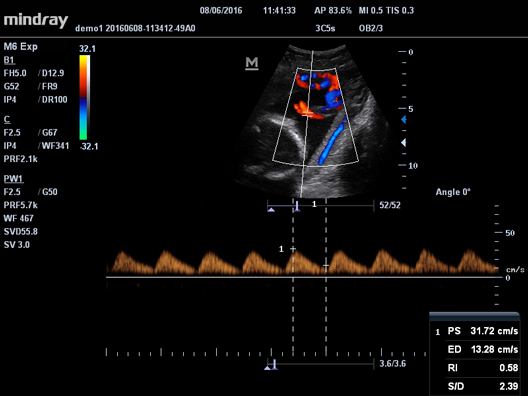

Клинические изображения Mindray M5 new

- B/M/Color Dopler/Color M/Power/Directional Power Doppler Flow Imaging

- PW Doppler, включая HPRF (High Pulsed Repitition Frequency)

- HR Flow - режим отображения кровотока с высоким временным и пространственным разрешением для точной и однородной визуализации сосудов, в том числе самых мелких